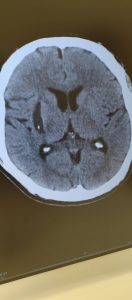

令和4年11月13日(日)に脳出血で倒れられた男性

翌日から個室に移り〇△□することができた方のCTスキャン結果です

左が搬送された時で、右が今日の結果です

この方は言語障害、左半身麻痺でした

リハビリ病院の予約がキャンセルになるほどで、11月25日に退院となった……あの症例です